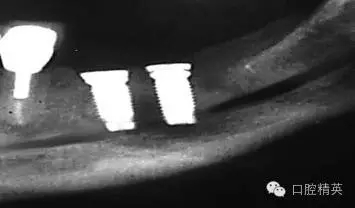

圖7a:6,7號(hào)牙種植體(3*15mm)折斷前,從物理學(xué)理論上講,種植體骨整合后,基臺(tái)螺絲和種植體相連接的支點(diǎn)處是受力時(shí)種植體最薄弱的位置。(a)可見6號(hào)牙種植體的折斷面,和7號(hào)牙種植體上的折裂線(b)。

圖7b:6,7號(hào)牙種植體折斷后。

種植體折斷可能發(fā)生于種植體行使功能幾年后,也可能發(fā)生于早期。(圖7a,b)對(duì)于圖中這一病例,治療計(jì)劃是在對(duì)患者的咬合關(guān)系,未來修復(fù)體理化環(huán)境,患者咀嚼習(xí)慣等充分評(píng)估后制定的。種植體折斷后,對(duì)該病例進(jìn)行了回顧性病因分析,上了頜架的模型揭示了過長(zhǎng)的頜間距離,和嚴(yán)重、廣泛的對(duì)頜牙磨耗(圖7c,d)。對(duì)于這一病例,醫(yī)生仔細(xì)評(píng)估了所有可得到的回顧性診斷信息,和患者進(jìn)一步討論交流后,提出了幾個(gè)診斷建議和一個(gè)過渡性治療方案,其中包括將固定修復(fù)改為鑄造可摘局部義齒。

考慮到取出種植體會(huì)造成很大的創(chuàng)傷,醫(yī)生提出了一個(gè)盡量避免增加創(chuàng)傷風(fēng)險(xiǎn)的折中治療方案。治療為:嚴(yán)密縫合關(guān)閉6號(hào),7號(hào)牙種植體周圍軟組織,將種植體埋入休眠。術(shù)后即刻戴入塑料過渡活動(dòng)義齒,術(shù)區(qū)軟組織穩(wěn)定后進(jìn)行鑄造可摘局部義齒修復(fù)。